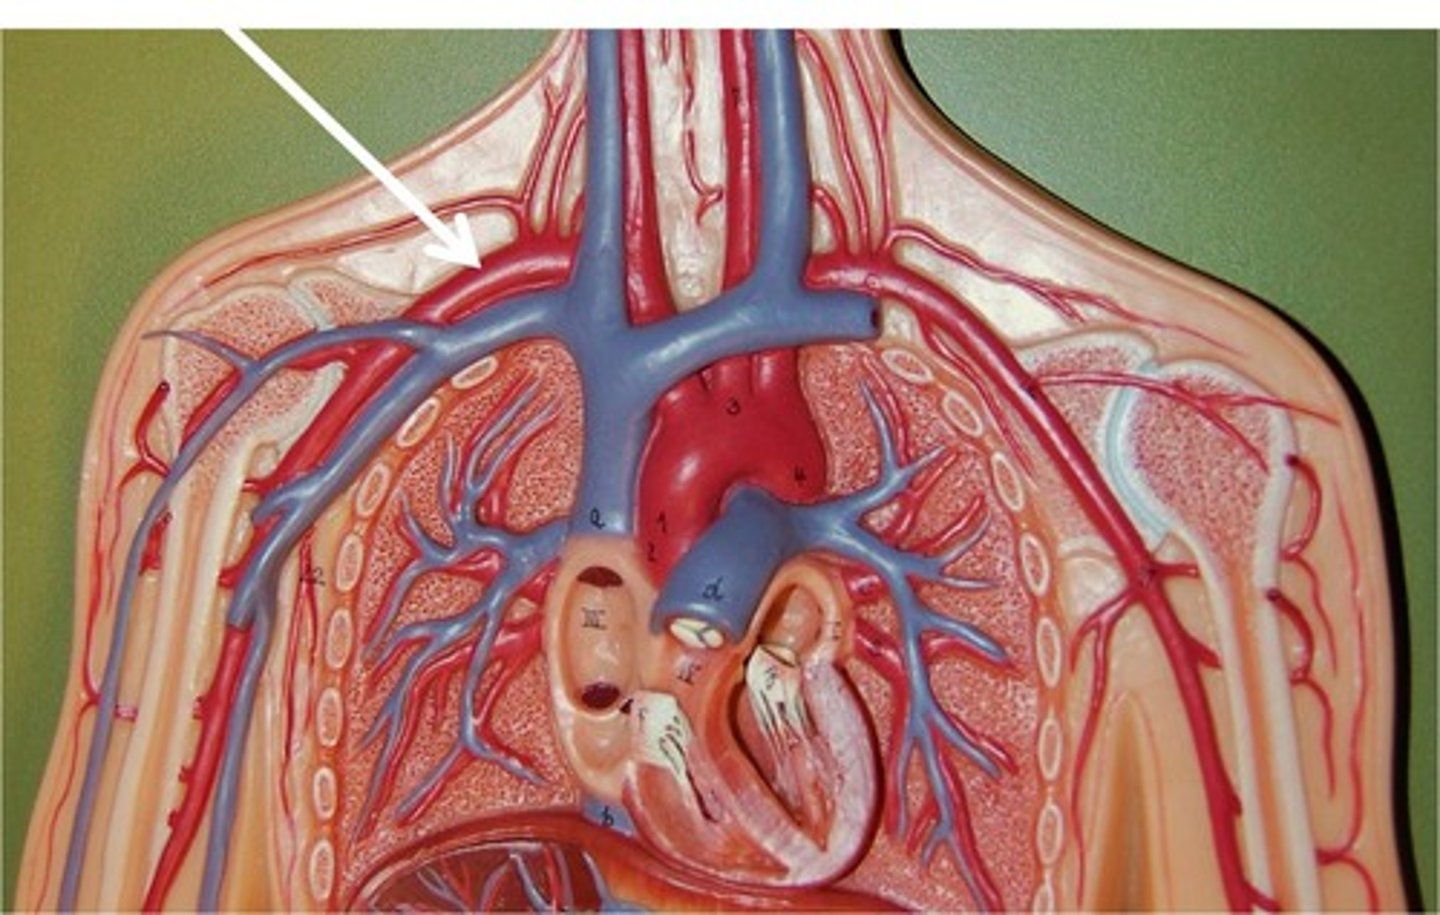

axillary vein

brachiocephalic vein

subclavian vein

axillary artery

flows into axilla, lateral chest, and shoulder joint

right subclavian artery

left subclavian artery